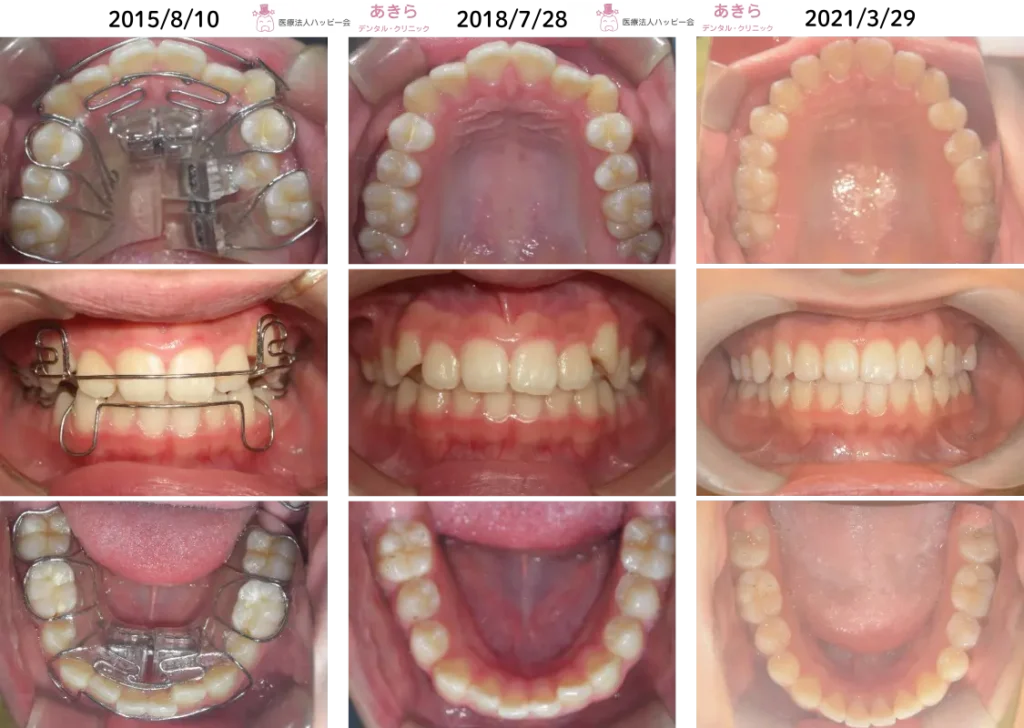

SH療法

SH療法-症例-No.004-特に前歯の凸凹が気になるケース

SH療法の概要 主訴 要望 初診 2016年1月9日⇒2022年5月14日 10歳11ヶ月⇒17歳3ヶ月 … -